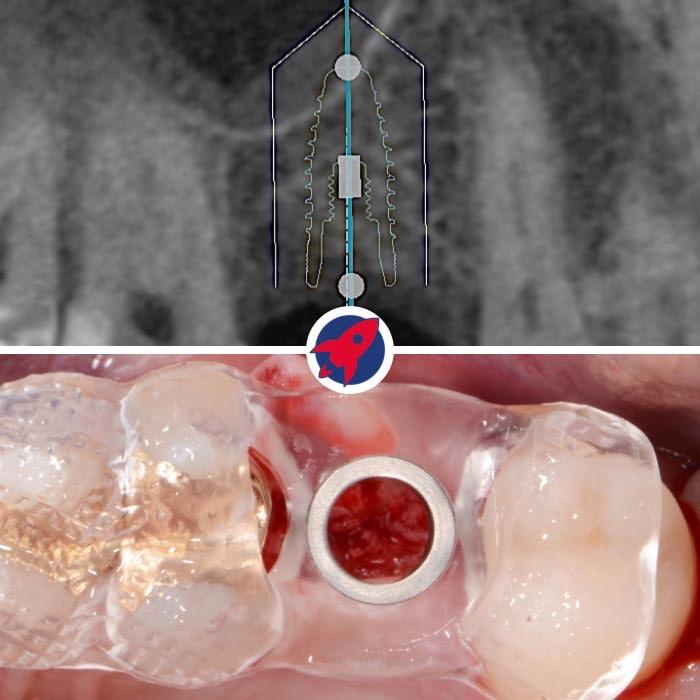

3D X-ray: Orthophos XG 3D

Safety begins with the right insight. Our Orthophos XG 3D provides us with a "transparent" view of your jaw. Unlike conventional 2D X-rays, we can see every anatomical structure in three dimensions. This allows us to plan procedures with millimeter precision and provide optimal protection for sensitive structures, such as nerve pathways.

The transparent jaw for your safety

High-resolution 3D images for precise planning and exceptionally gentle treatments.